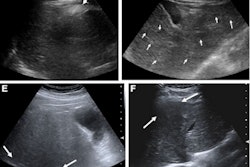

Ultrasound images depict a 56-year-old man with obesity (body mass index, 42) and steatosis (MRI-PDFF, 10.4%), who underwent ultrasound attenuation coefficient (AC) measurement due to participation in the present study. The unit displays color-coded confidence map (left) and AC map (on right) in side-by-side manner. The confidence map indicates quality of acquired AC signals and is set like traffic lights: green indicates good quality acquisition, yellow indicates warning, and red indicates low quality. Areas with low quality are left blank on the AC map. The image shows multiple circular ROIs placed at depths below the liver capsule of 2, 2.5, 3, and 4 cm. All ROIs are 3.5 cm in size. The confidence map threshold is set at 20%. AC measurements (in units of dB/cm/MHz) were extracted from all ROIs (excluding voxels without assigned color on the AC map) and decrease with greater ROI depth.ARRS